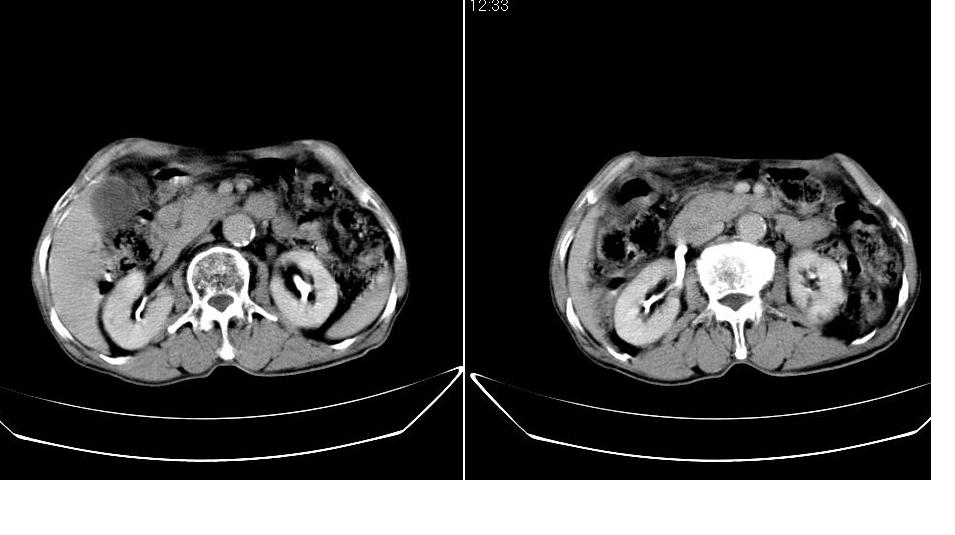

男,76岁,上腹部疼二天来就诊,彩超提示肝左叶占位,随后做上腹部ct平扫,今天做上腹部ct增强扫描,手工推药,效果不好,请谅解。

肝左叶s4肿块强化形式大概是:慢进慢出,逐渐强化----考虑血管瘤/腺瘤?{动脉期应更提前扫}。

肝右叶前段hcc

1)肝右叶前段低密度灶,不排除肝癌可能;建议查afp。2)右肾上极囊肿。

肝内胆管积气扩张,胆囊增大,肝右前叶低密度灶,逐渐强化,一元论,胆系感染,局限性肝脓肿;右肾囊肿。

考虑肝s4段肝脓肿可能?未排除肝癌。右肾上极囊肿。